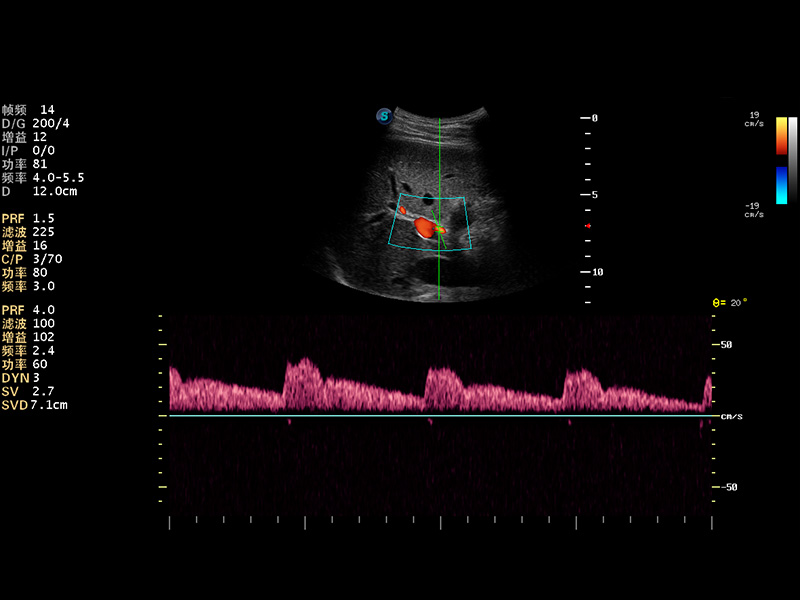

超声彩色多普勒诊断仪

2014年,开立医疗推出了全身应用型超声彩色多普勒诊断仪S22系列,在成像技术、人体工程学设计及工作流优化等方面,以卓越的临床图像、稳定的产品性能、齐全的应用功能充分满足几乎所有的科室的临床诊断需求。